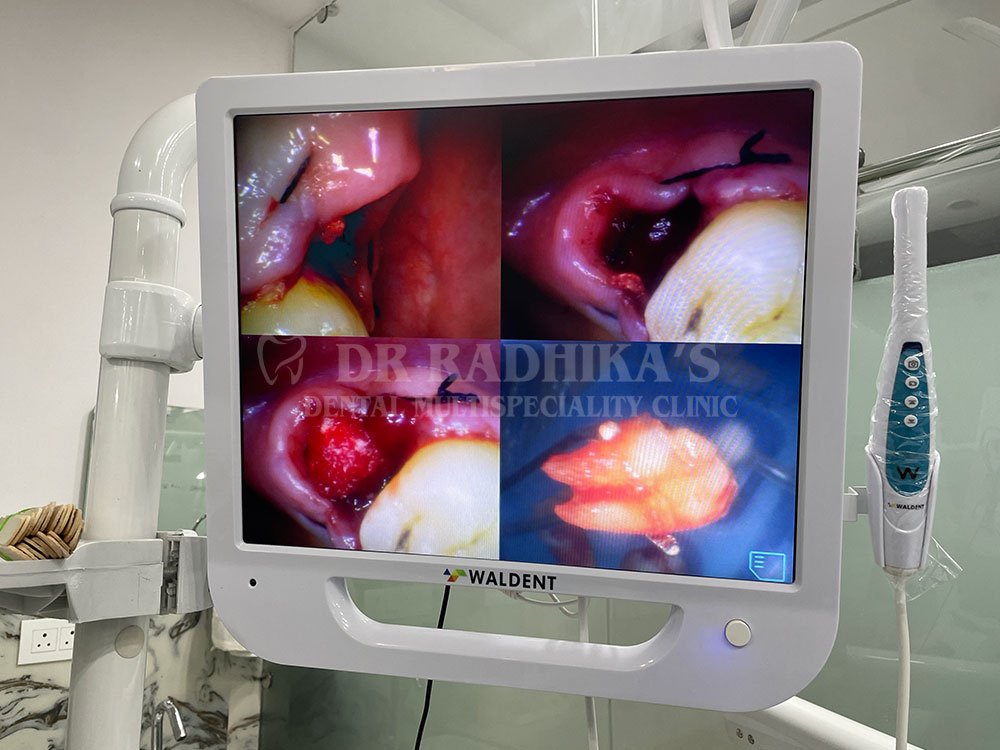

At Dr. Radhika Multispecialty Clinic, we combine clinical expertise with compassionate care. Our skilled dental surgeons are trained to perform both simple and surgical extractions, including the removal of impacted wisdom teeth and complex root extractions. With our advanced diagnostic tools like digital X-rays and CBCT scans, we can identify the exact position of the tooth and plan the safest and most efficient extraction.

Patient comfort is our top priority. We offer local anesthesia and sedation options (if required) to ensure you remain relaxed and pain-free during the procedure. We also follow strict sterilization protocols and use state-of-the-art instruments to ensure safety and accuracy in every treatment.